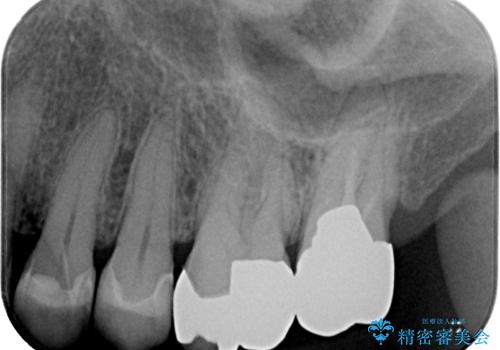

銀歯が取れた セラミックインレー修復

- 銀歯が取れたとのことで来院された患者様です。咬み合わせが強い方なので、ゴールドインレーでの治療をお勧めしましたが、ご本人の希望により審美性に優れたセラミックインレーでの治療を行っていくことにしました。

拡大鏡視野下で、保険のプラスチック、虫歯の除去を行い、セラミックインレーに適した形に整えました。

歯と歯茎の間に圧排糸と言われる糸を入れてシリコーン印象材にて精密な型どりをしました。

セラミックインレーの装着時には、唾液の侵入を防ぐために、ラバーダム防湿を行いました。